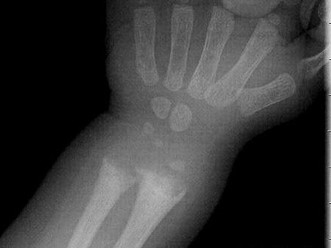

[单选题]男,10岁,有外伤,根据所提供图像,选择最佳选项 ( )A.未见异常B.骺移骨折C.青枝骨折D.腕关节脱位E.踝关节脱位